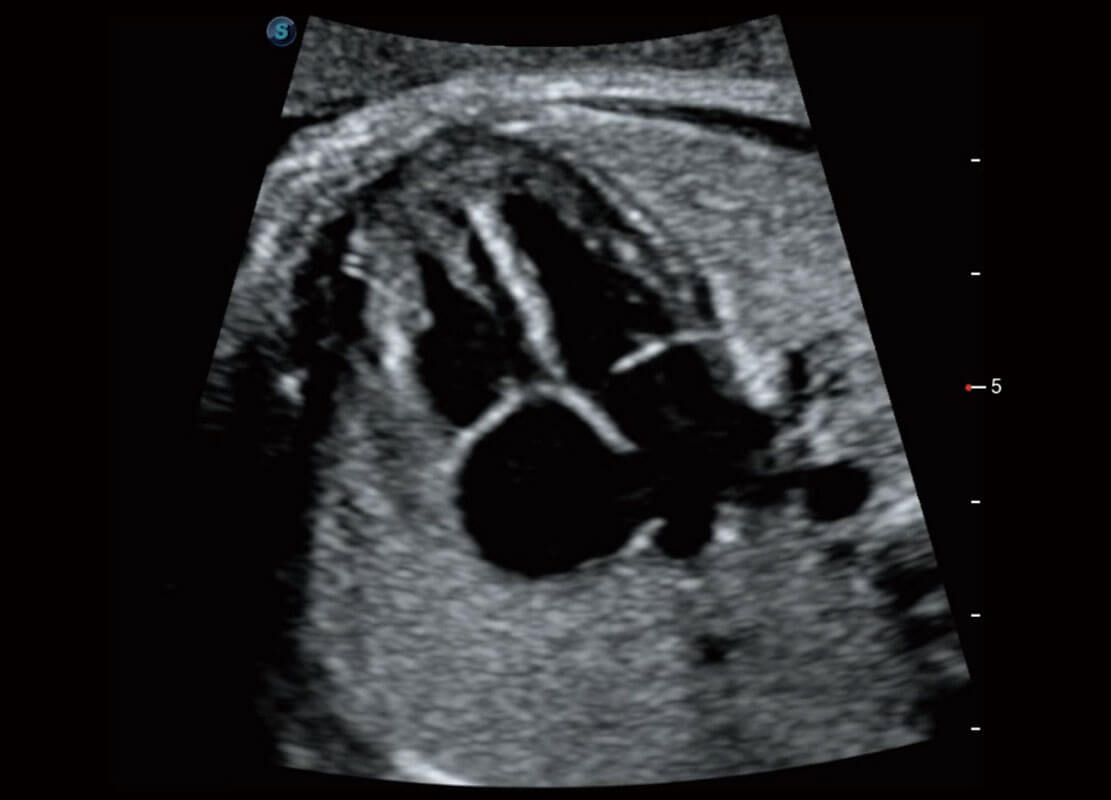

腔内三维-宫内节育器

腔内三维-光影成像